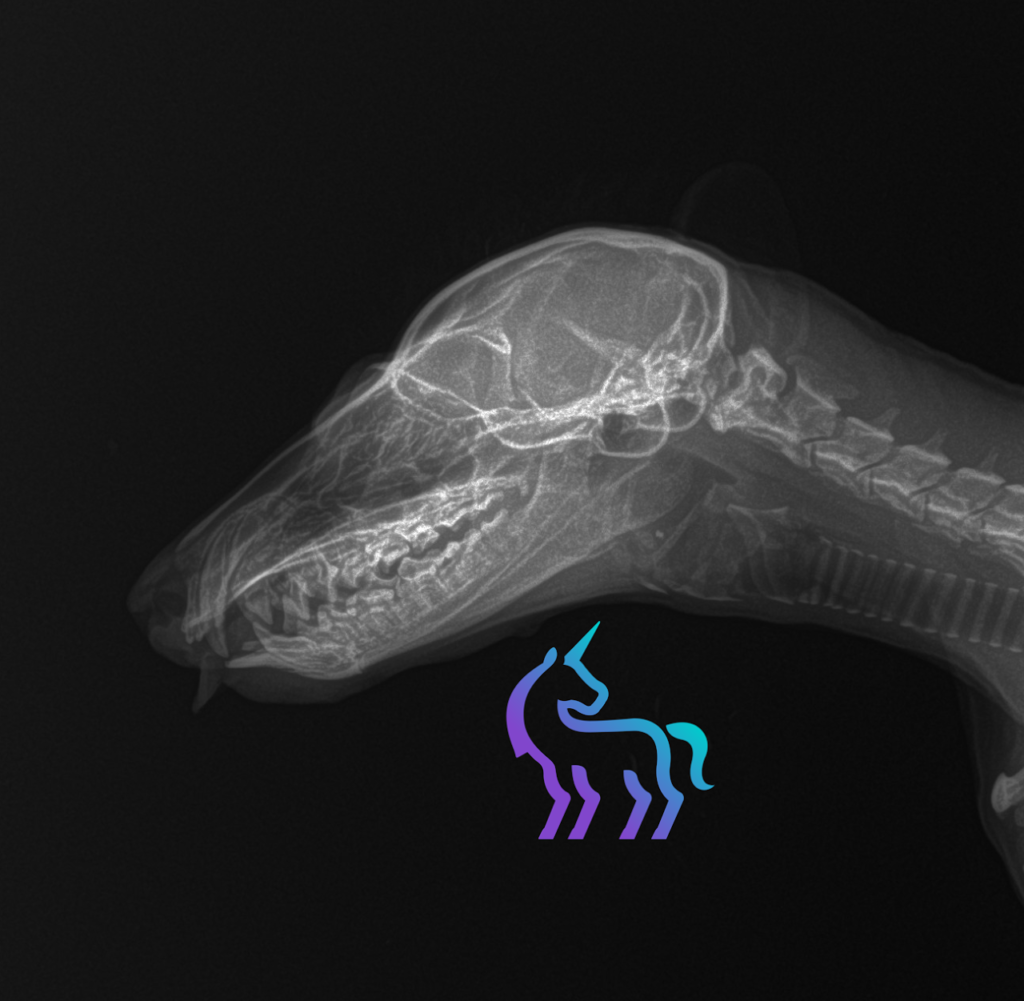

Radiographie tête de renard © Lingostière Clinique Vétérinaire dans l’Art Radiographique